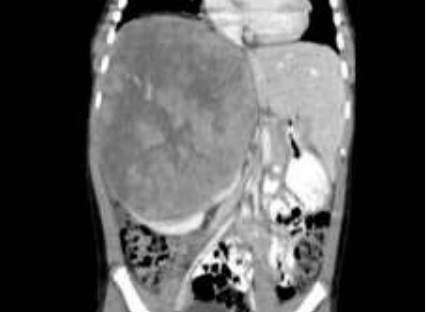

Menino, 5 anos, negro, admitido no Pronto Socorro com a queixa de aumento do volume abdominal, sem dor ou demais sintomas associados. Realizada Tomografia Computadorizada de abdome que evidencia a seguinte imagem:

Coletadas catecolaminas urinárias com VMA=10 e VMA=15.

Sobre a principal hipótese diagnóstica, assinale a afirmativa incorreta.